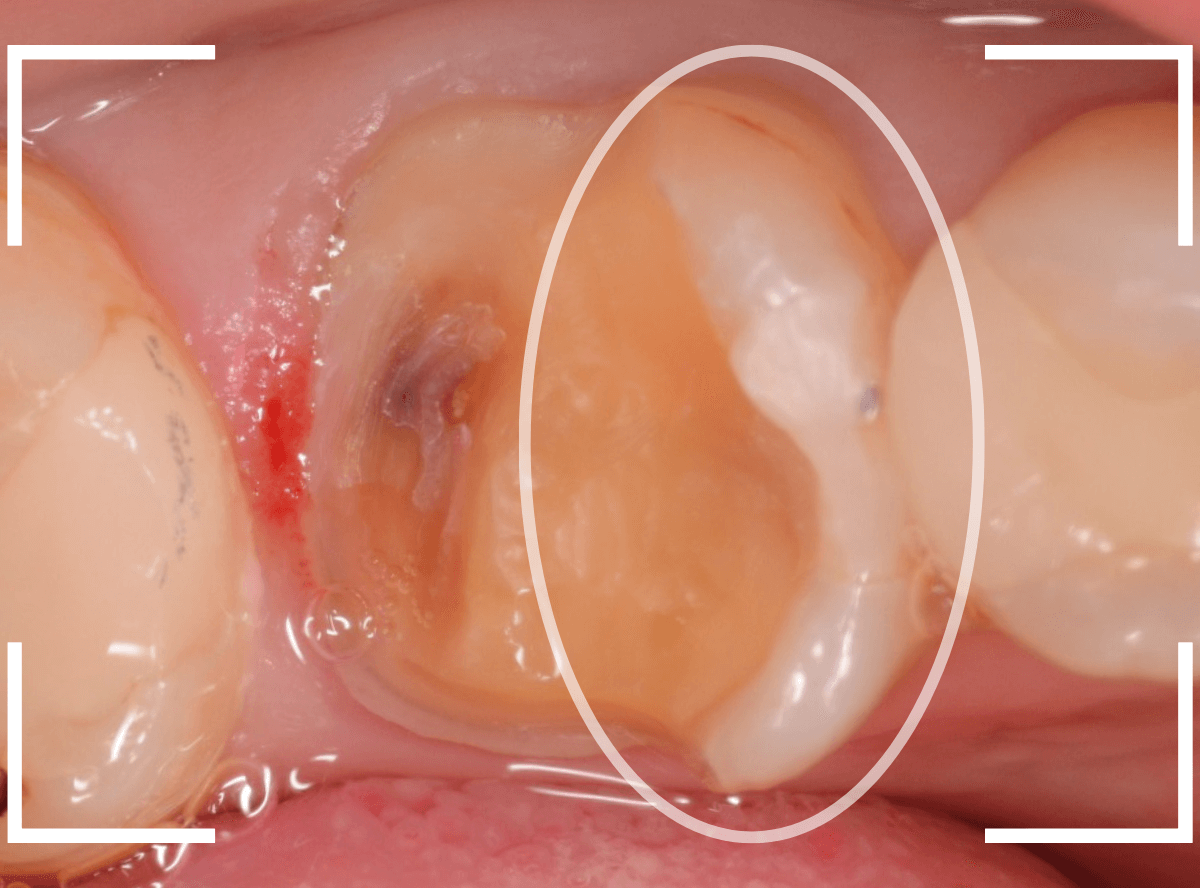

さし歯を入れるスペースがない!

一番奥の歯が土台(コア)の治療までで中断してしまってる患者さんの例です。

本来であれば、この上にさし歯を作らなければいけないのですが、この時点でかみ合ってしまい、さし歯を作ろうにも作りづらい状況でうやむやのうちに治療中断になってしまったようです。

まず、土台の治療をしてから時間が経過していることと、不適合になっている事から、外して中を調べます。

すると、土台の中で虫歯にもなっていました。

(〇部の赤い部分)

こういった事は、レントゲン写真でもよくわからない事が多く、土台を外す治療は本当に神経を使います。

今回は、歯肉の中まで歯が欠損しているので、このまま土台とさし歯を作り直しても、いい結果にはなりません。

患者さんに状況を説明し、歯の周りの歯肉を麻酔をして電気メスでトリミングします。